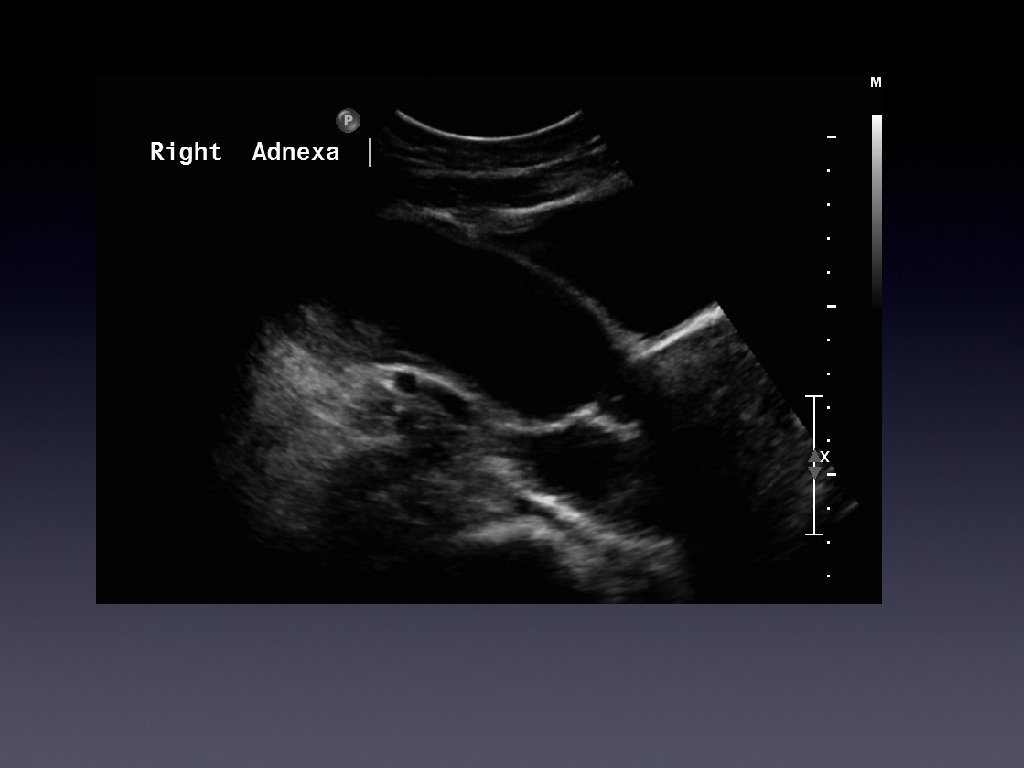

Presentation • • • 36 year old female Presented with chronic right iliac fossa

Presentation • • • 36 year old female Presented with chronic right iliac fossa pain Tenderness on palpation Bloods normal Investigated further with a pelvic ultrasound

Learning Points • • • Hydrosalpinx is usually a tubular cystic mass However it

Learning Points • • • Hydrosalpinx is usually a tubular cystic mass However it has septations Septations are caused by the normal fold present in the fallopian tube which become thickened with inflammation.

Learning points • • • Usually a cystic mass Variable internal echogenicity Devoid of

Learning points • • • Usually a cystic mass Variable internal echogenicity Devoid of septations Can have debris Not every tubular mass in the iliac fossa is ovarian in origin!!!!